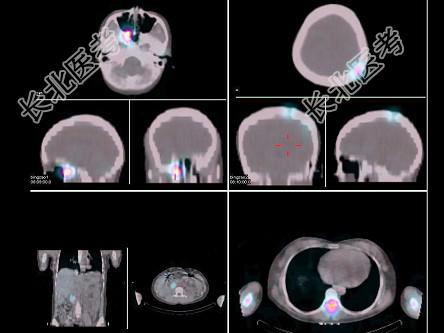

- [材料题] 女,22岁,阵发性高血压2年,间歇性头痛、胸背痛半年,CT示右肾门区占位病变,行¹³¹I-MIBG全身显像+局部X线定位及⁹⁹Tcᵐ-MDP骨显像如图